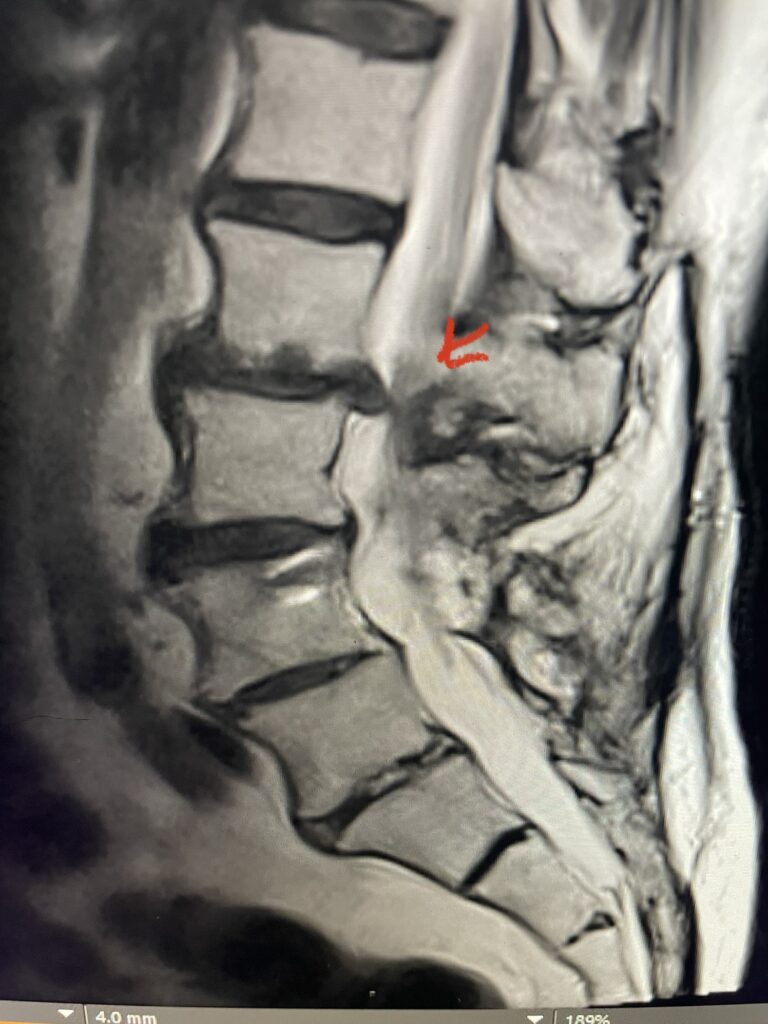

Fig 2: Coronal lumbar CT demonstrating L4-S1 fusion with instrumentation with some incomplete bony fusion to the L3-4 segment (red arrow)

The patient had failed all means of conservative management including Physical Therapy and epidurals. He had an extensive medical history including stroke, cardiac stents, diabetes on insulin, hypertension, hypercholesterolemia, and kidney disease. Since he had a prior fusion with instrumentation for L4-S1, it was interesting that the patient had not developed significant next segment stenosis at L3-4. However, CT analysis (Fig. 2) demonstrated a partial fusion that extended from L3 to L4 which prevented abnormal motion.